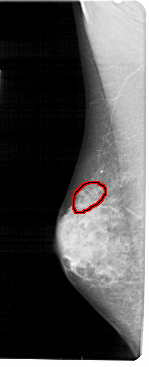

A_1937_1.LEFT_CC

LEFT_CC LINES 4891 PIXELS_PER_LINE 2281 BITS_PER_PIXEL 12 RESOLUTION 43.5 OVERLAY

FILE: A_1937_1.LEFT_CC.OVERLAY

TOTAL_ABNORMALITIES 1

ABNORMALITY 1

LESION_TYPE CALCIFICATION TYPE PLEOMORPHIC DISTRIBUTION CLUSTERED

ASSESSMENT 4

SUBTLETY 3

PATHOLOGY BENIGN

TOTAL_OUTLINES 1

BOUNDARY